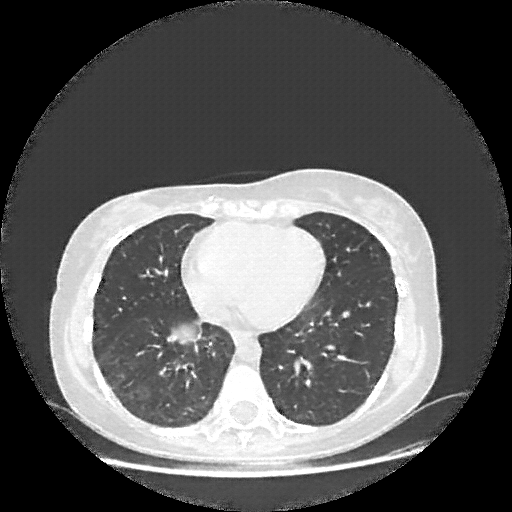

Image Grid

4Γ—3 grid: Rows show different image types (Original NATIVE, Reconstructed NATIVE, Original VENOUS, Generated VENOUS), Columns show windowing techniques (No Window, Lung Window, Mediastinum Window)

Original VENOUS CT scan

Lung window (WL -600, WW 1500 β†’ Low βˆ’1350, High +150)

Mediastinum window (WL 40, WW 400 β†’ Low βˆ’160, High +240)

Generated VENOUS CT scan (A→B translation)